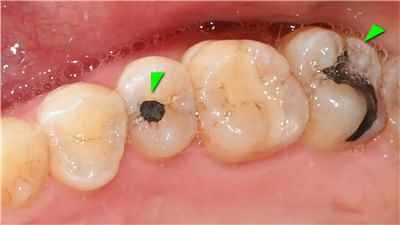

치아 변색 내부 원인